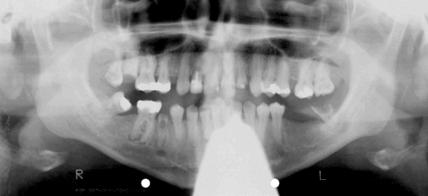

Therapie einer behinderten Patientin unter Hypnose

In der vorliegenden Kasuistik wird die oralchirurgische Behandlung einer durch einen Hirntumor körperlich und geistig behinderten Patientin geschildert, die anstatt einer ursprünglich empfohlenen Behandlung in Narkose eine Therapie unter kombinierter Lokalanästhesie/Hypnose wünschte. Trotz erheblicher ärztlicher Bedenken erwies sich die Patientin als ausgezeichnet trancefähig und erlebte die Behandlungssitzungen nahezu stressfrei. Eine ausgedehnte chirurgische Zahnsanierung konnte

Therapie einer mehrfach behinderten Patientin unter klinischer Hypnose

Jahr 2007, Ausgabe 03, Seite 22 Autoren: Priv.-Doz. Dr. med. dent. Dr. med. Dirk Hermes, Dr. med.Jutta Stec/Lübeck*, Priv.-Doz. Dr. med. Ludger Bahlmann/Höxter**, Priv.-Doz. Dr. med. Stephan Klaus/Münster-Hiltrup***